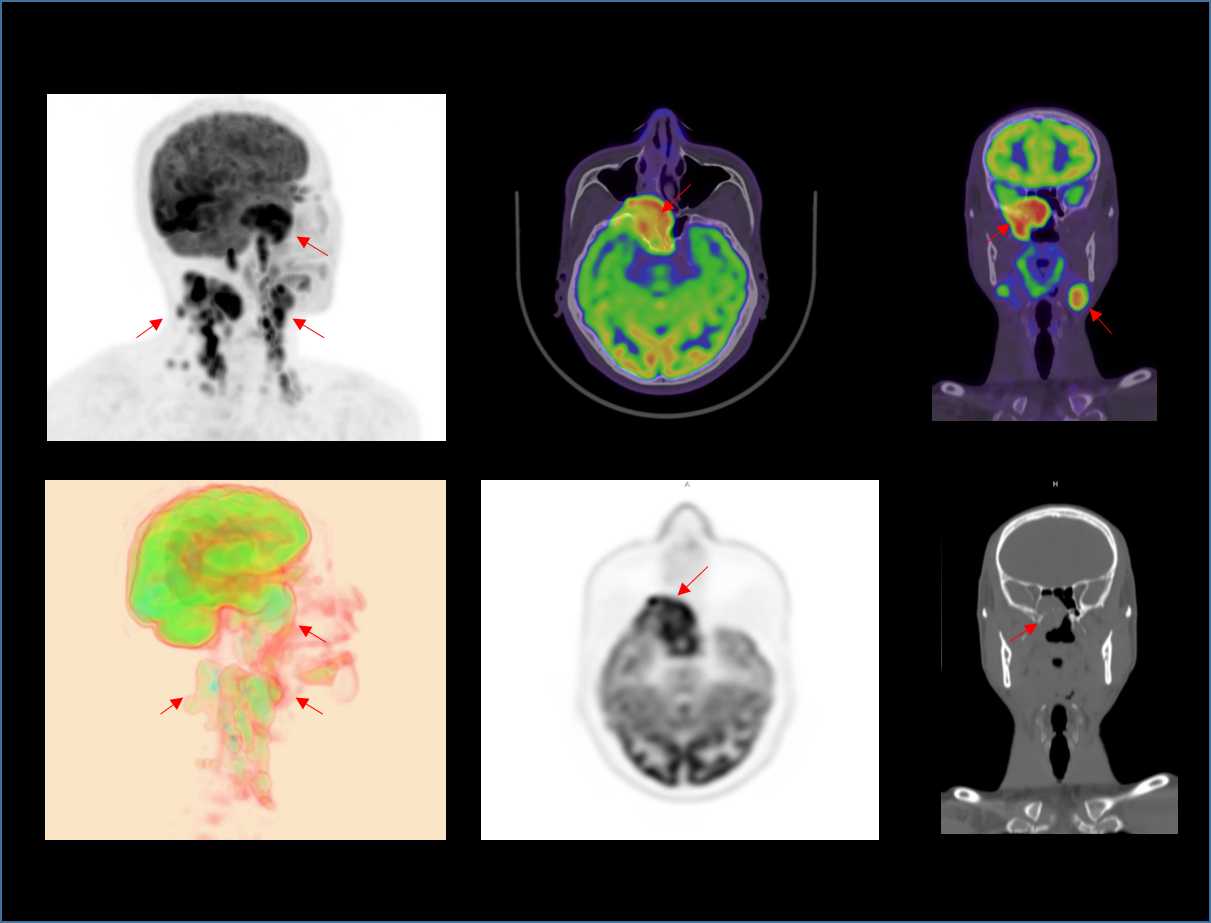

微小病灶无以遁形